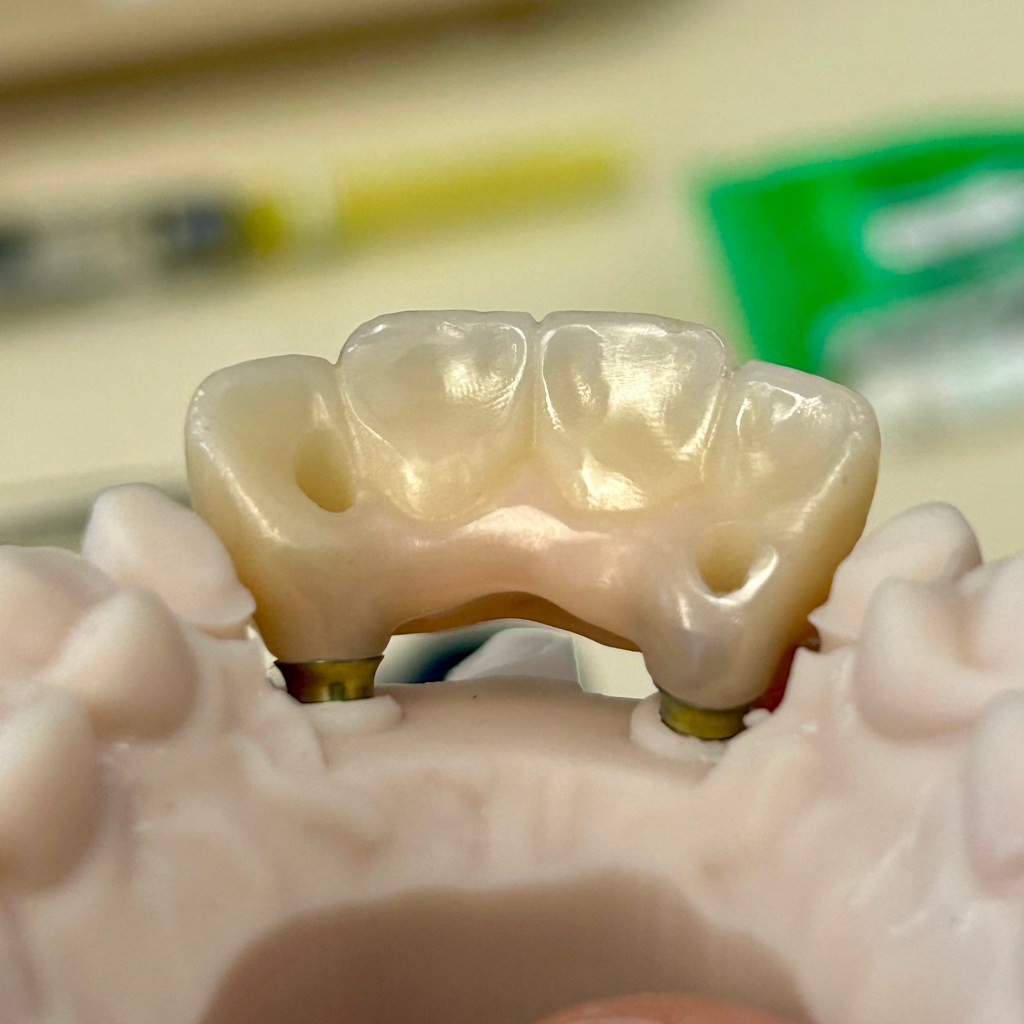

Ceramic Bridge